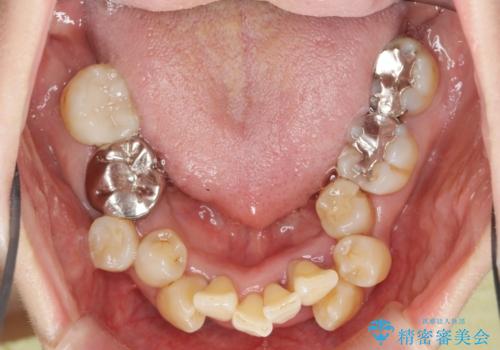

- 重度の歯周病に罹患しており、他院で「多数の歯を抜歯したのち、入れ歯を入れるしかない。」と言われ、入れ歯以外の方法がないか相談のため来院されました。

重度の歯周病で多数の歯を残せない問題、歯並び・噛み合わせの問題、欠損の問題、と多数の大きな問題が認められました。